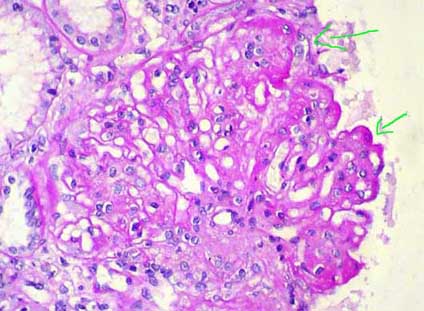

Figure 6. In some cases there are sclerosing segmental lesions (arrows). This finding not necessarily indicates a worse prognosis (PAS, X.400).

When advancing the process the material that forms the spikes increases and surround completely the deposits, forming thus new layers of GBM leaving the deposits immersed in this material. Now the deposits are seen intramembranous and with silver stain capillary walls can take an aspect in “chain” or “rosary”. This evolution point of the glomerular changes is known as STAGE III. The deposits continue being positive with the immunostaining (IF), although progressively they are less electron-dense (Figures 7 and 8).

Figure 7. When advancing the process of the disease the parietal immune deposits are progressively surrounded by GBM-like material, which gives an irregular aspect in chain or “rosary” to the GBM (arrows); these findings characterize stage III of the MGN. According to the predominant alteration in the capillary we diagnose the lesions as stage I, II, III, or IV. (Methenamine-silver, X1000).

Figure 8. In this microphotography is possible demonstrate better the capillary wall lesions in stage III MGN; see as the material that appears in the external part of the GBM (black with the silver) forms circles or ring that completely surrounds the immune deposits (arrows). (Methenamine-silver, X1000).